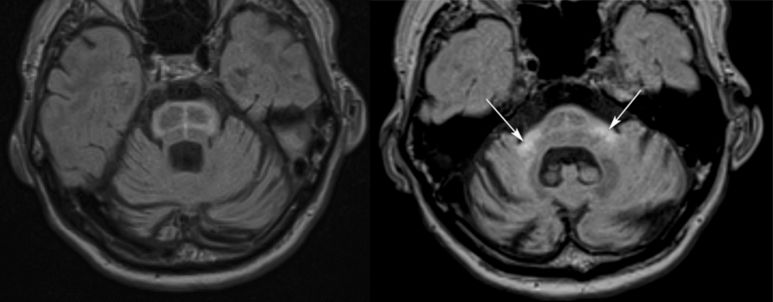

PSP中小腦上腳萎縮